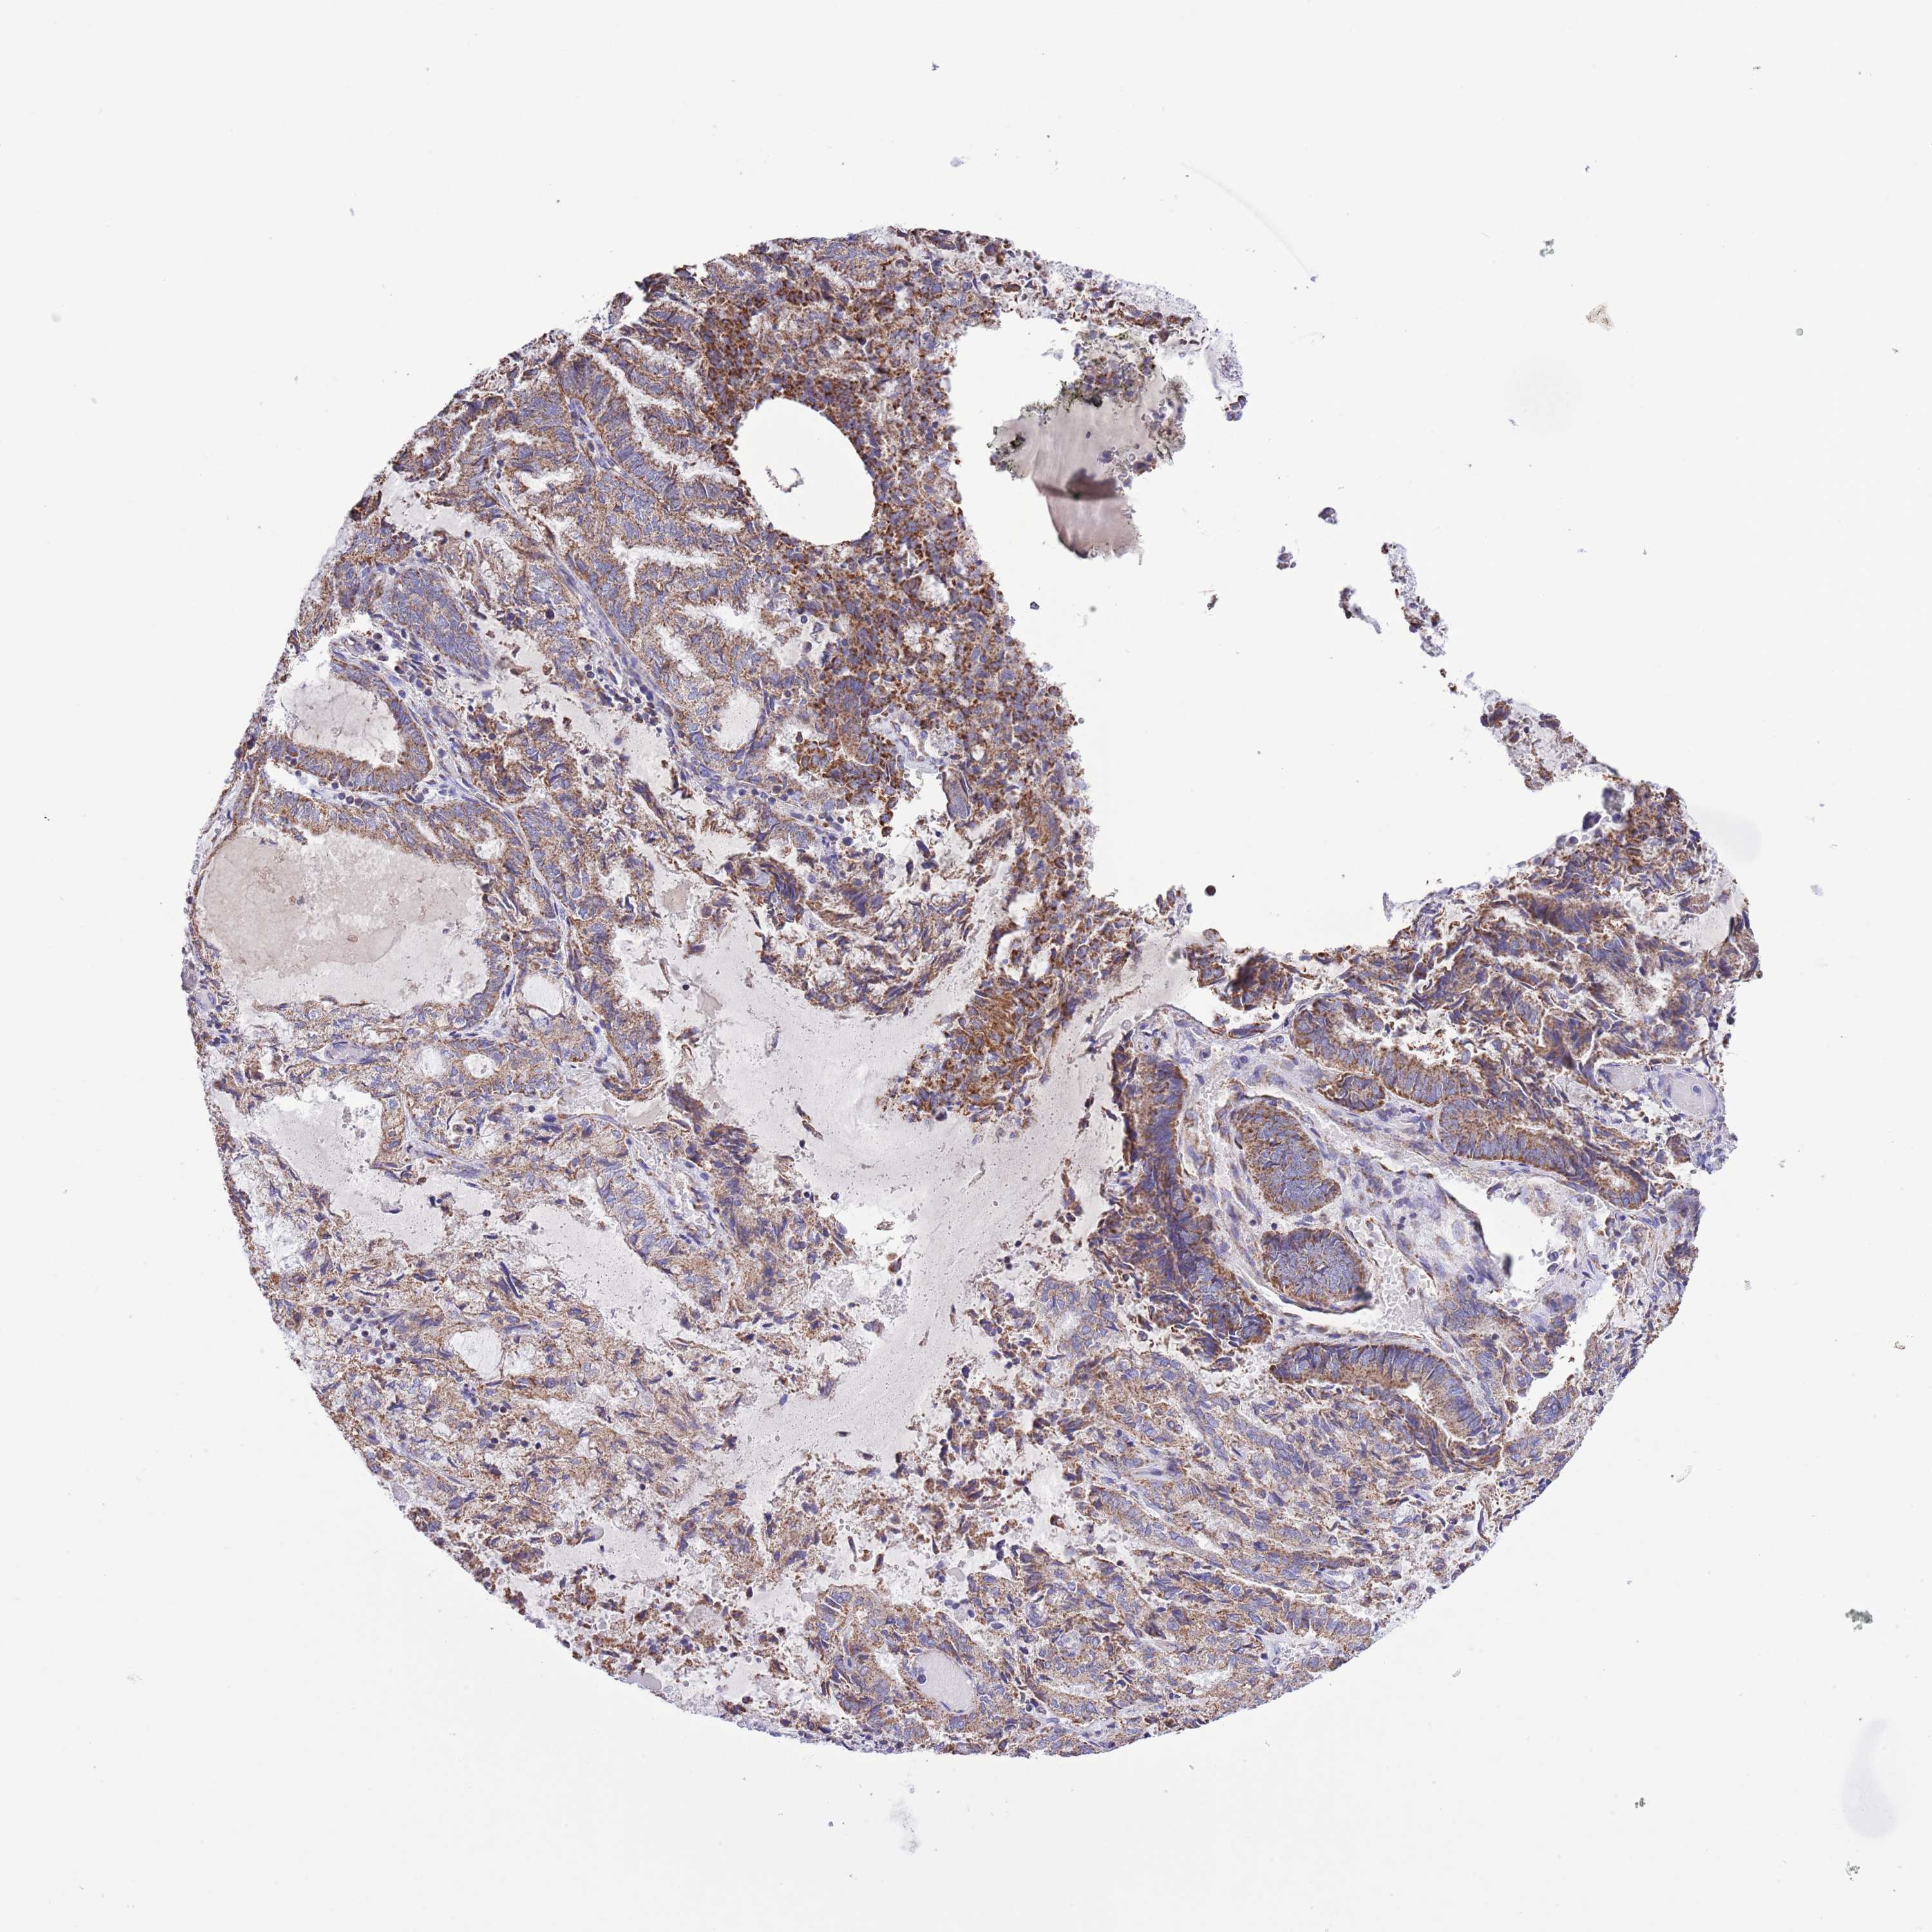

ENDOMETRIAL CANCER - Protein expressioni

A mouse-over function shows sample information and annotation data. Click on an image to view it in a full screen mode. Samples can be filtered based on level of antibody staining by selecting one or several of the following categories: high, medium, low and not detected. The assay and annotation is described here.

Note that samples used for immunohistochemistry by the Human Protein Atlas do not correspond to samples in the TCGA dataset.

Antibody stainingi

Antibody staining in the annotated cell types in the current human tissue is reported as not detected, low, medium, or high, based on conventional immunohistochemistry profiling in selected tissues. This score is based on the combination of the staining intensity and fraction of stained cells.

Each image is clickable and will lead to virtual microscopy that enables deeper exploration of all samples and also displays staining intensity scores, fraction scores and subcellular localization as well as patient and tissue information for each sample.

Antibody HPA048654

Staining

High

Medium

Low

Not detected

Intensity

Strong

Moderate

Weak

Negative

Quantity

>75%

75%-25%

<25%

None

Location

Nuclear

Cytoplasmic/membranous

Cytoplasmic/membranous,nuclear

Adenocarcinoma, NOS